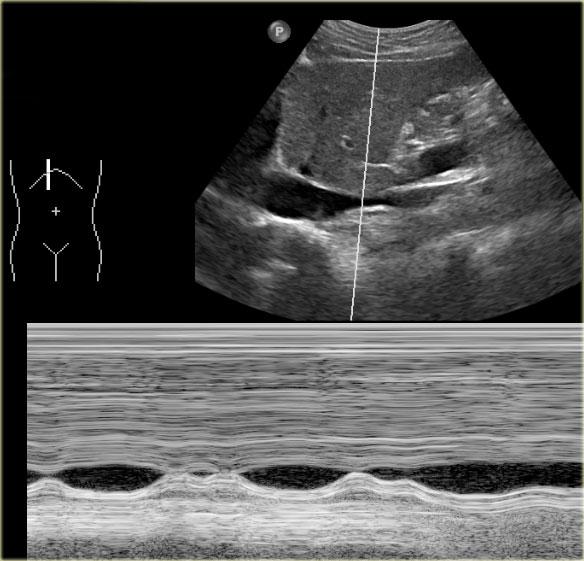

Dấu hiệu siêu âm trong suy thất phải:

- Giãn tĩnh mạch chủ dưới (IVC) và tĩnh mạch gan

- Gan to

Trong điều kiện bình thường, siêu âm động học sẽ cho thấy sự thay đổi khẩu kính của tĩnh mạch chủ dưới.

Những thay đổi khẩu kính này có thể được lý giải bởi sự biến thiên lưu lượng máu trong tĩnh mạch chủ dưới theo chu kỳ hô hấp và chu kỳ tim.